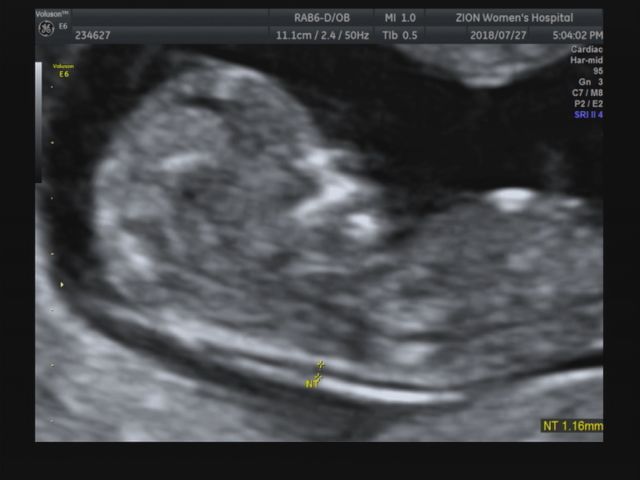

2019.01.04 +34주 6일 이날은 막달검사 하는 날! 분만 전에 채혈, 소변검사, 심전도, 엑스레이 검사를 통해...